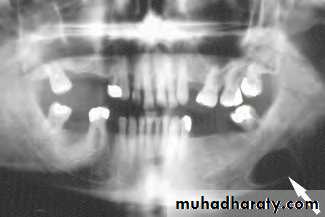

sialolithiasis; the most common cause of obstruction 80%, because the submandibular secretions usually viscus.80% radio-opaque and can identified by x-ray

C/F: painful swelling, precipitated by eating , the swelling occurs rapidly and resolve spontaneously over 1-2 hrs.(meal time syndrome)

The most common sites of impaction are the of the gland and near the punctum.

Examination: enlarged firm tender swelling. Pus may be visible from sublingual papilla or expressed by bimanual palpation.